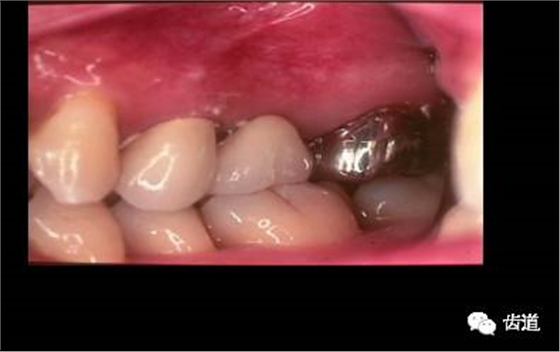

六)外形(contour):

符合生理要求及解剖特點(diǎn)

七)美觀(esthetics):

位置、形態(tài)、排列、色彩與鄰牙及整個牙列協(xié)調(diào)